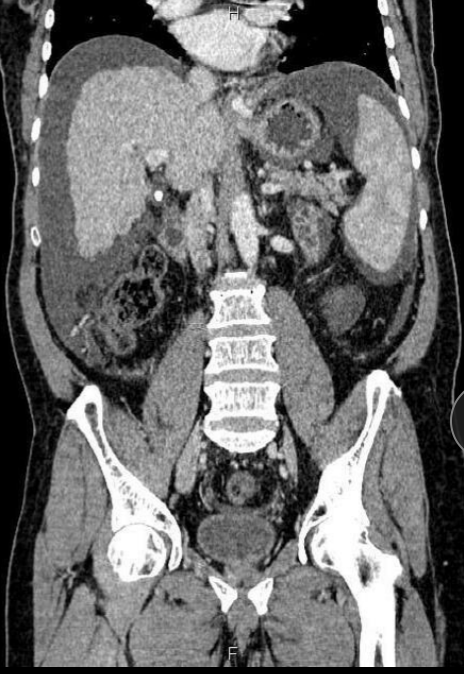

7

Q

A

Hígado graso